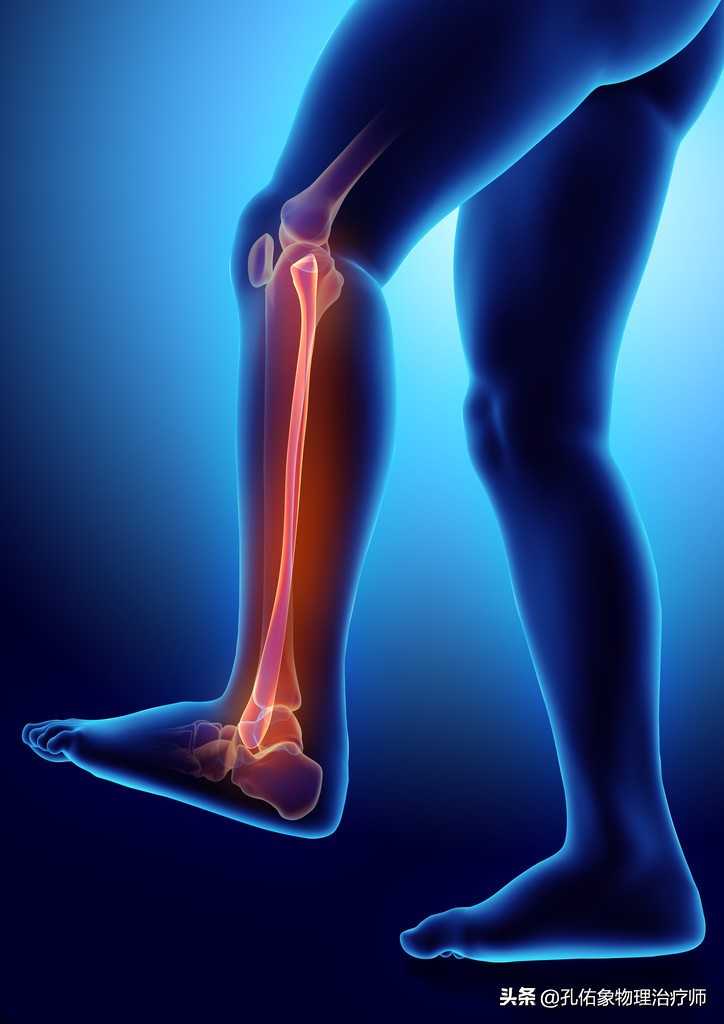

2.足底疼痛

当你膝盖出现疼痛,走路自然而然就会出现疼痛步态,为了躲避疼痛而行走,就会改变身体结构的力学负荷,引起脚巴掌的受力不均匀而出现踝足的肿胀疼痛;到医院去拍片检查,也会发觉什么问题也看不出来,还是正常的,就是疼痛,就是查不出具体的原因,有可能就是膝痛的导致的。

因为膝痛,会使稳定膝盖骨周围的韧带、肌肉打破原有的平衡;比方说现在很多人因不注意锻炼,常见于大腿外侧很紧,而膝盖骨内上缘处的股内侧斜肌就会很弱,从而影响到膝的受力,就会导致小腿发生旋转,最终使脚巴掌发生受力不均的情况下行走,毫无疑问就会出现足底疼痛。